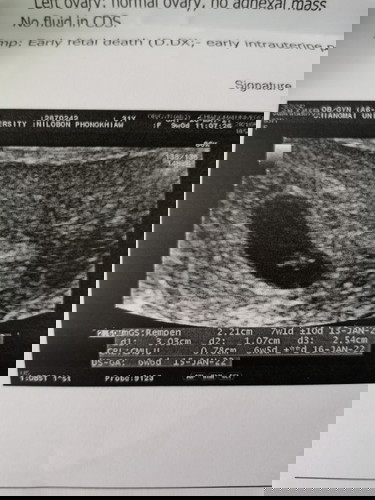

#ขอคำแนะนำหน่อยค่ะ เราหาหมอครั้งแรก 4w ซาวด์ทางช่องคลอดไม่เจออะไร หมอนัดต่อ 6w ซาวด์ทางช่องคลอด เจอถุงตั้งครรภ์และจุด หมอว่าเป็นถุงไข่แดง หมอนัดต่ออีก 8w ครั้งนี้ซาวด์ผ่านหน้าท้อง เจอถุงตั้งครรภ์ที่ใหญ่ขึ้น แต่ตัวอ่อนวัดได้แค่ 0.78cm. หมอว่ามีขนาดเท่ากับ 6w และไม่เจอหัวใจ หมอว่าน้องอาจเสียในครรภ์ไปแล้วค่ะ ให้ยุติการตั้งครรภ์ เราควรรอต่อไปมั้ยคะ เผื่อว่าจะเจอหัวใจน้อง หรือเชื่อหมอและยุติคะ?